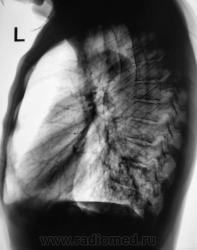

Пациент направлен на рентгенографию ОГК с диагнозом - "Левостороняя пневмония".

Анамнез стандартный. Ранее неоднократно страдал обострениями хронического бронхита. Сейчас вот не нашутку занемог - температура до 38, откашливает мокроту, кашель продуктивный.

Диагноз левосторонней нижнедолевой С10, С9 сементарной пневмонии наверное будет верным, а с учётом фона- с наличием бронхоэктазов.